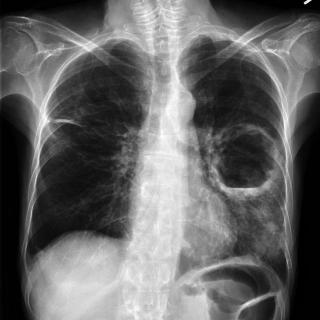

Плоскоклеточный рак представляет собой злокачественную опухоль, которая развивается из плоского эпителия и при этом сохраняет способность к кератинизации в различной степени, поэтому клинические проявления и темпы прогрессирования заметно зависят от органа-источника, глубины инвазии и биологических свойств опухолевых клеток.